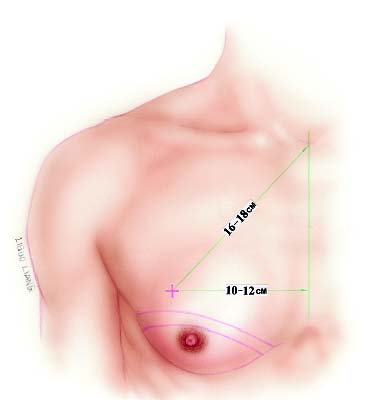

Patients with large breasts and MWL patients have in common a large amount of excess skin that cannot be managed in one stage without an incision beyond the areola. Additionally, the pedicled procedures preserve subareolar volume to achieve appropriate contour. The procedure described in this chapter employs an inferior pedicle similar to the reliable one utilized widely in female reduction mammoplasty. Subcutaneous mastectomy is accomplished to remove excess tissue, preserving the upper flap, which is advanced over the pedicle to the inframammary fold. An opening is cut in the flap to admit the nipple–areola. In addition to providing blood supply to the nipple–areola, the pedicle favorably augments the contour above the inframam-mary fold. MWL patients often display large skin excess that extends laterally to the axilla and arm. The lateral inframam-mary incision can be extended posteriorly to provide skin excision and contour correction in these areas.